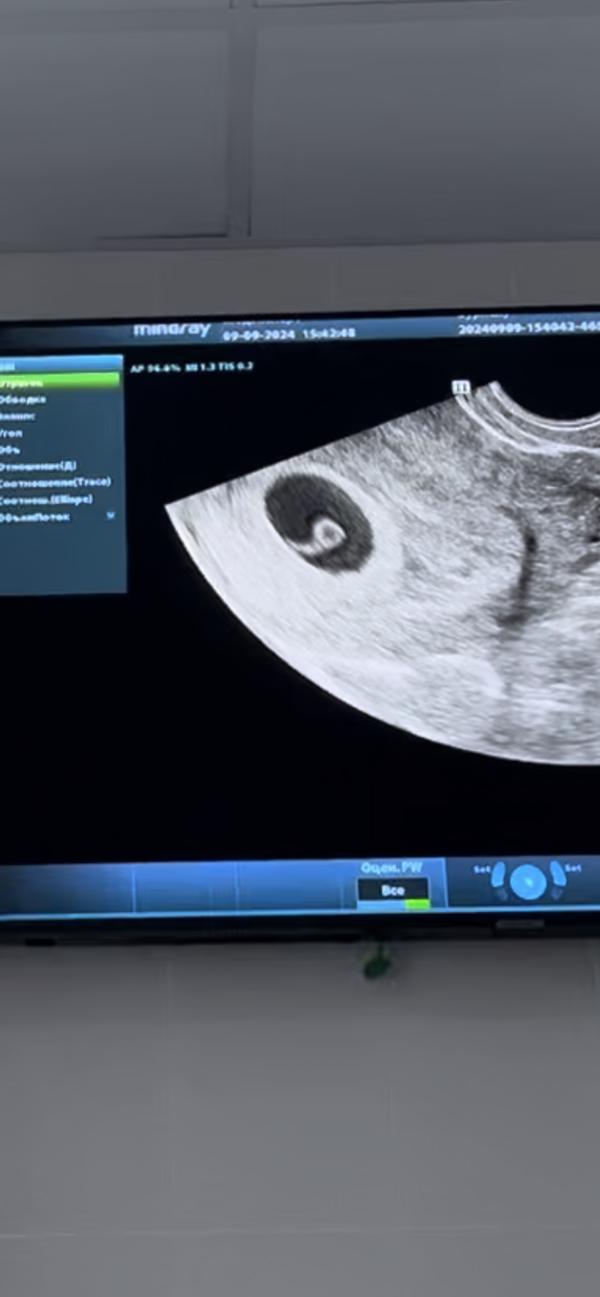

Узи на раннем сроке: что увидели? 09.09.2024, малыш здоров!

post image 2

Сделали узи ранней беременности!

09.09.2024

Мы здоровенькие❤️